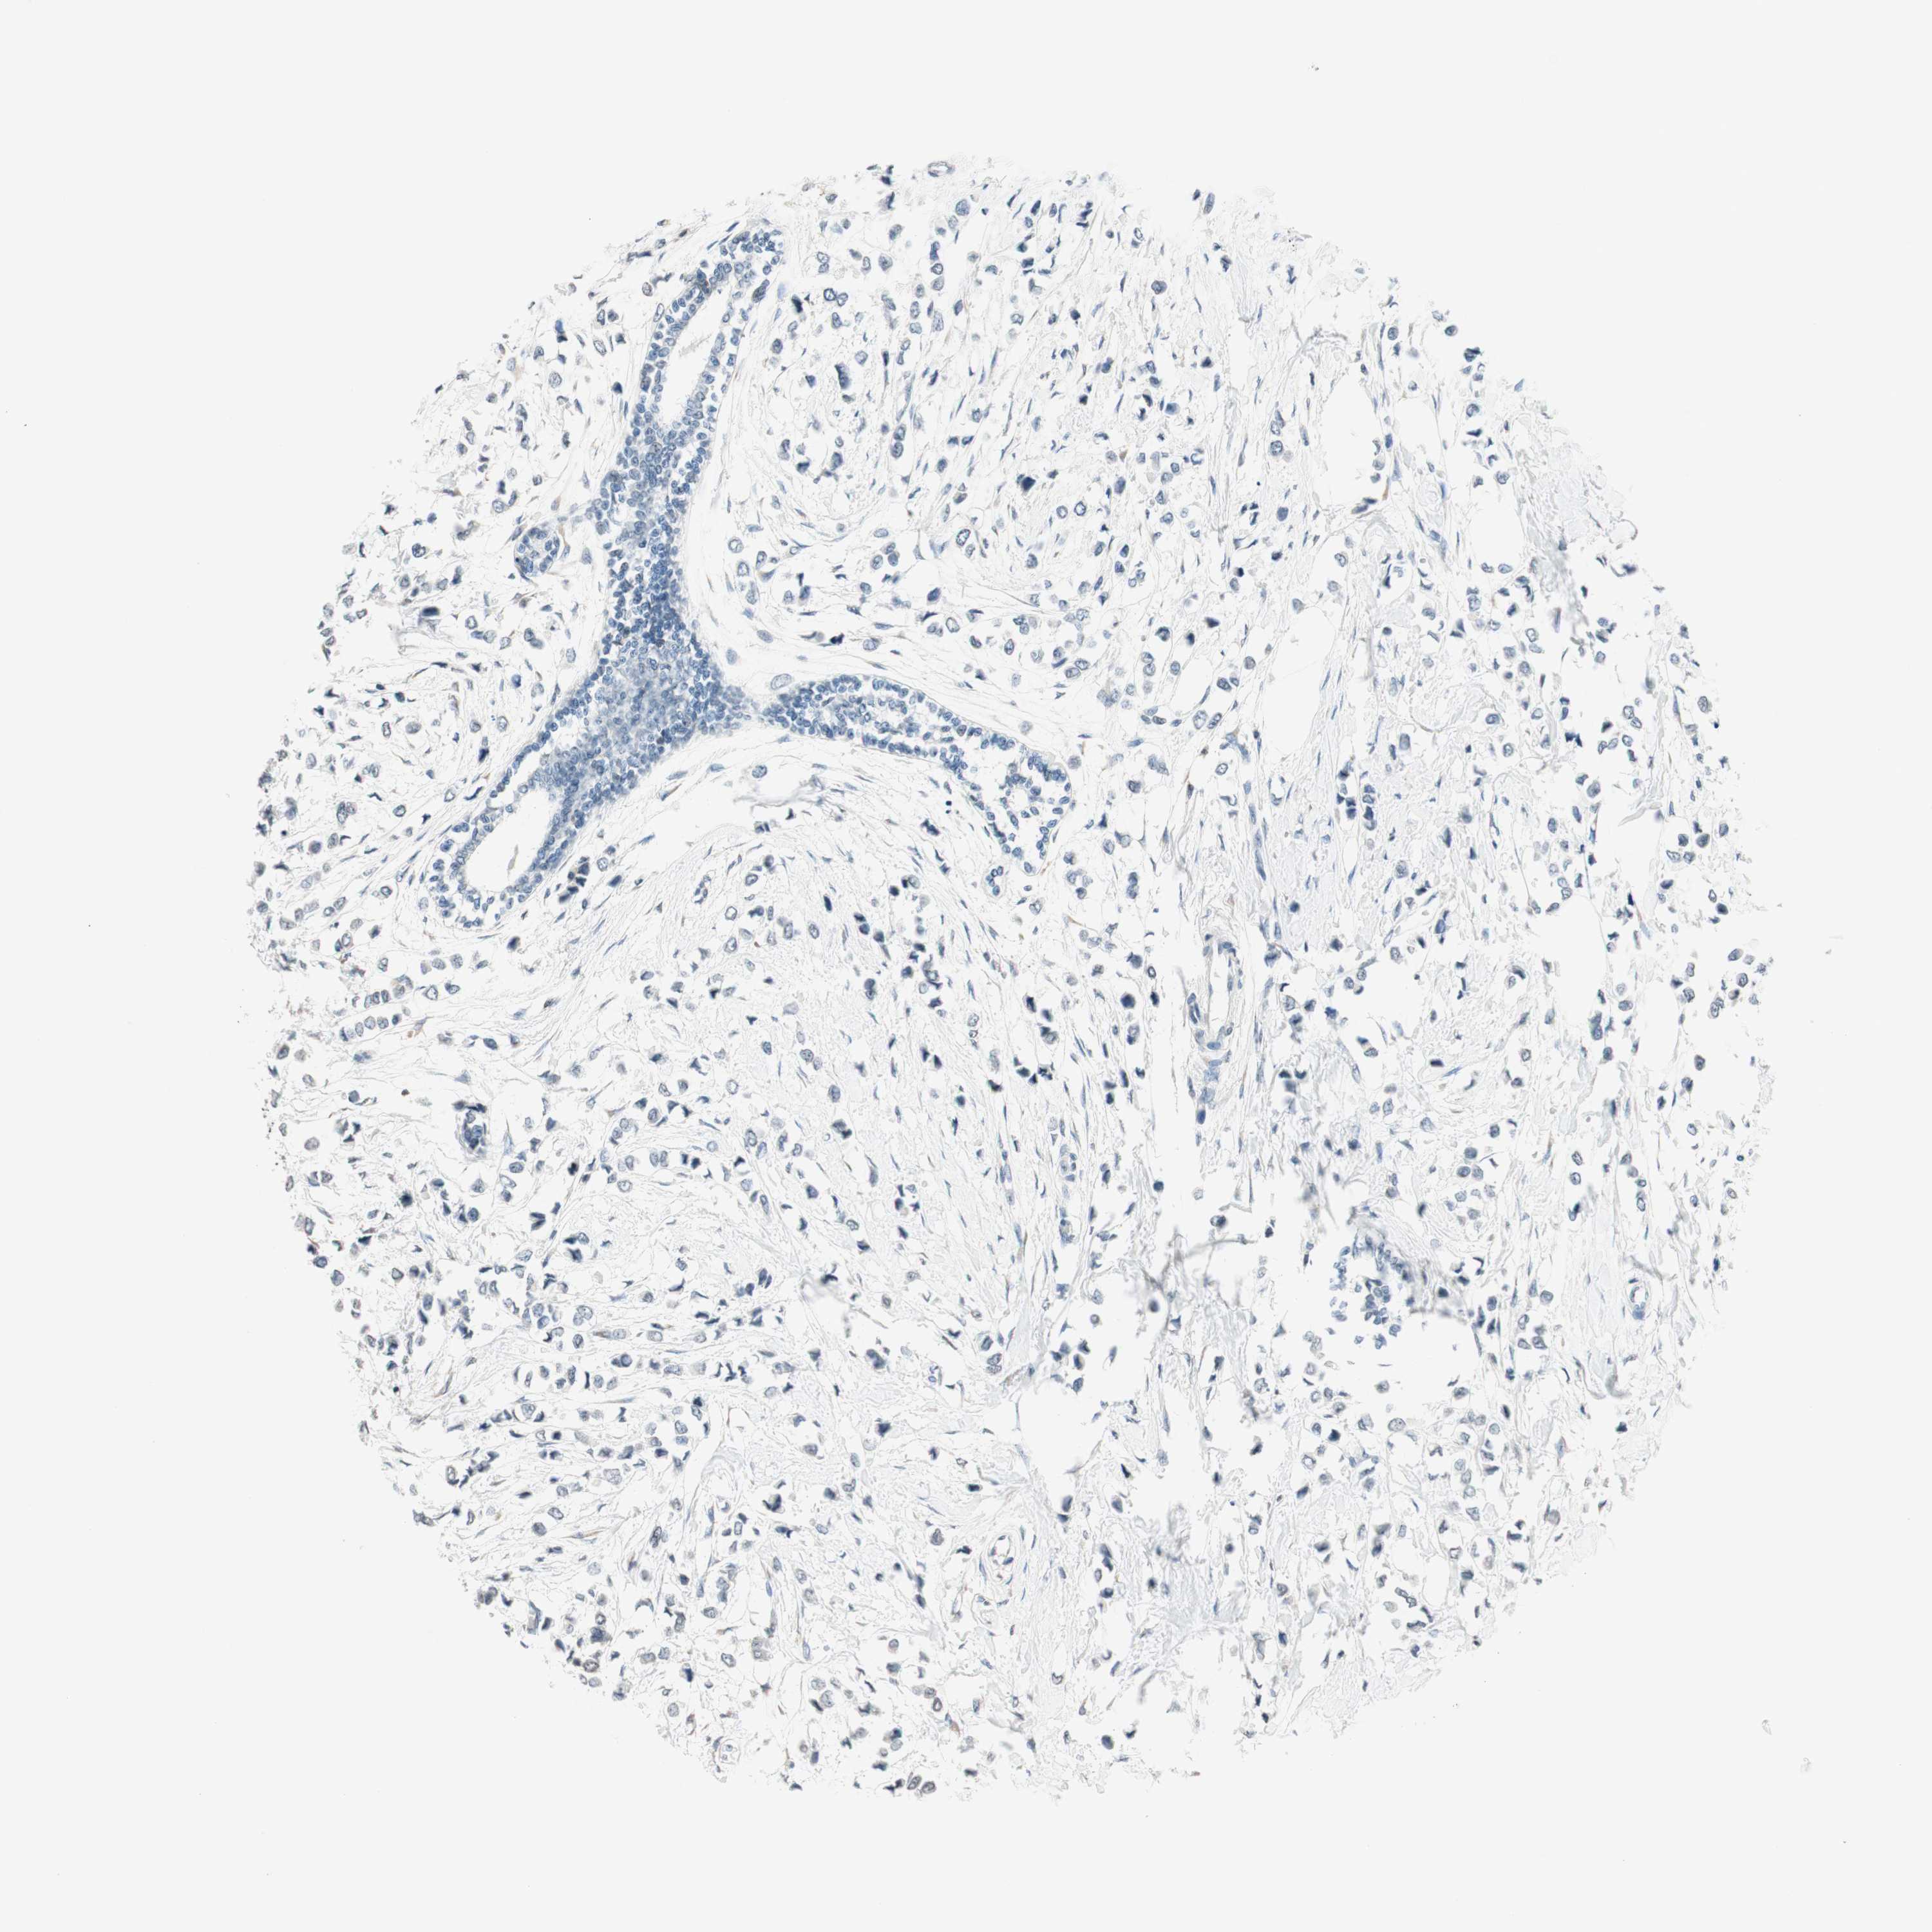

BRCA TCGA BRCA VALIDATION PROTEIN EXPRESSION

ANTIBODIES

AND

VALIDATION